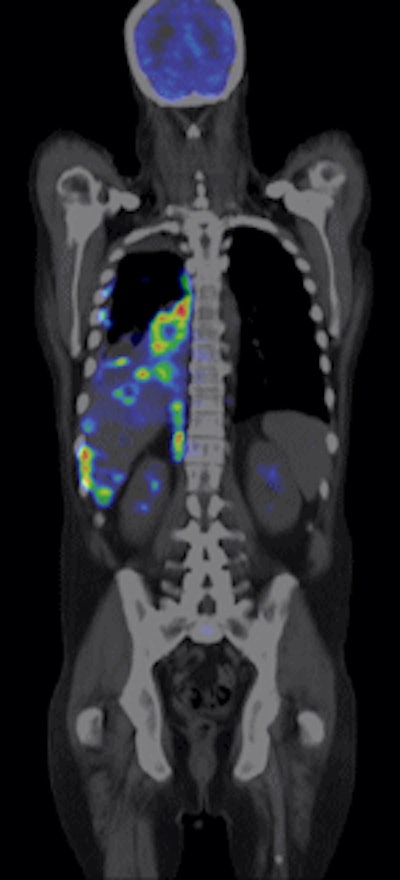

![]() |

| The color PET images are overlaid on a CT scan to show the exact location and extent of disease. The image is from GE Healthcare's Discovery PET/CT 600. Image courtesy of GE and the Cancer Treatment Center of America of Tulsa, OK. |